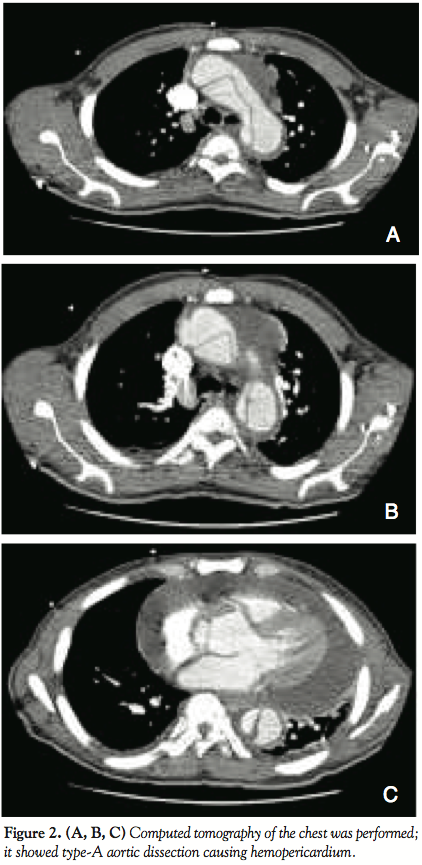

Laboratory work-up showed white cell counts of 7,800 cells/ml with normal differentials, platelets of 234,000/ml and hemoglobin of 9.4 mg/dl. Basic metabolic panel was unremarkable. Chest x-ray was done and showed enlarged heart size with obscured left lower lobe with superimposed density effusion (Figure 1). Computed tomography of the chest was performed and showed type-A aortic dissection causing hemopericardium (Figure 2). The cardiothoracic surgery team was consulted and the patient was immediately taken for emergency operation. The patient underwent surgery and experienced a successful outcome.